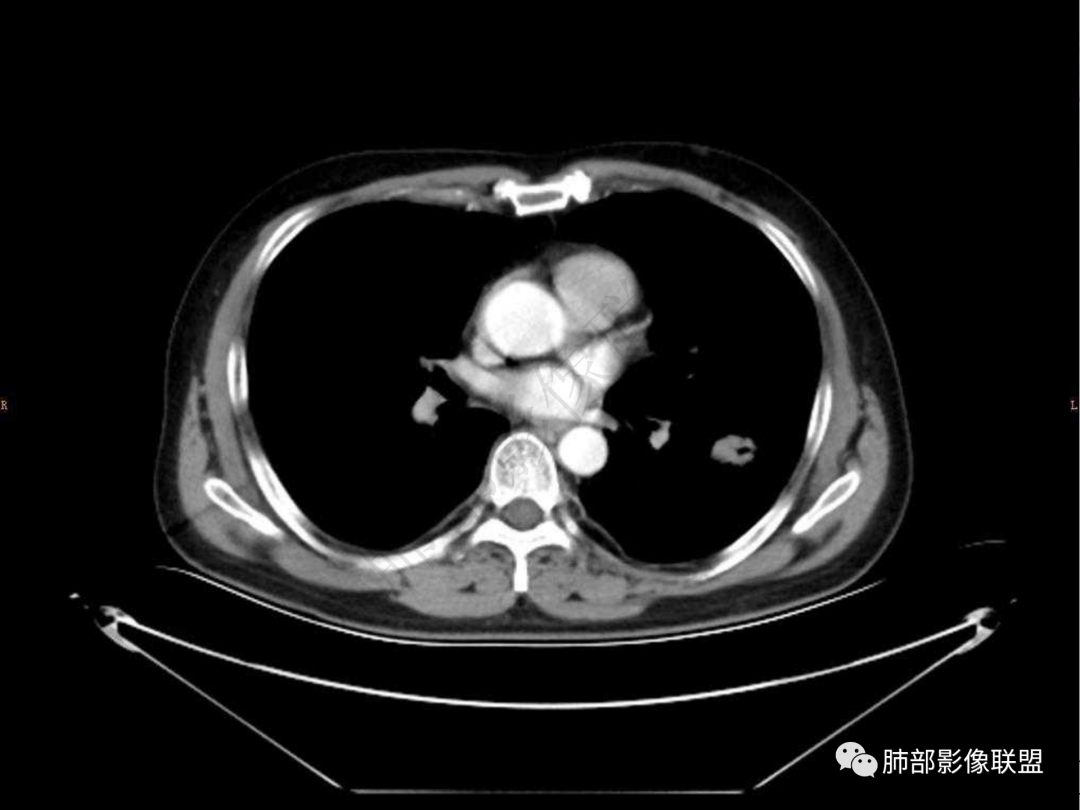

1.中年男性,咳嗽咳痰20余天,间断咯血2周

2.左肺下叶团片影,跨背段及内前基底段,实性部分类椭圆形,密度不甚均匀,可见毛刺及棘状突起,未见典型分叶及胸膜凹陷。病灶上下缘可见相应肺段支气管旁进侧出,管壁轻度增厚,未见狭窄阻塞。

3.周边较大范围磨玻璃影,边界相当模糊,小叶增厚明显。注意叶裂另一侧、左肺舌段亦可见磨玻璃影及增厚的小叶间隔。未见明确卫星病灶。

4.实性部分不均匀环形强化并显示一小范围低密度坏死区或空洞。较之肺窗,整体纵隔窗范围较小,提示病灶并不十分密实。抑或为不同时段图像。

5.双肺门及纵隔未见增大淋巴结。未见胸腔积液。